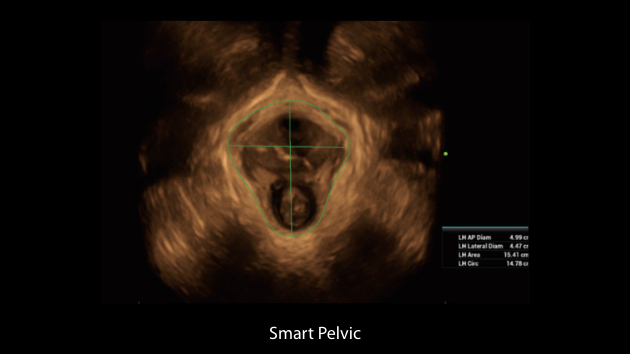

Nuewa I9 Elite Edition ├© progettato appositamente per l'assistenza sanitaria a donne e neonati e offre un'esperienza innovativa sviluppata sulla base di conoscenze approfondite relative a scenari clinici complessi, per risposte accurate e tempestive, nonch├® un'efficienza e un'esperienza utente eccezionali